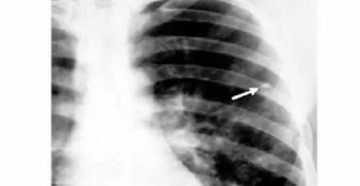

Очаги в лёгких на КТ — что это может быть и как выглядят очаговые изменения…